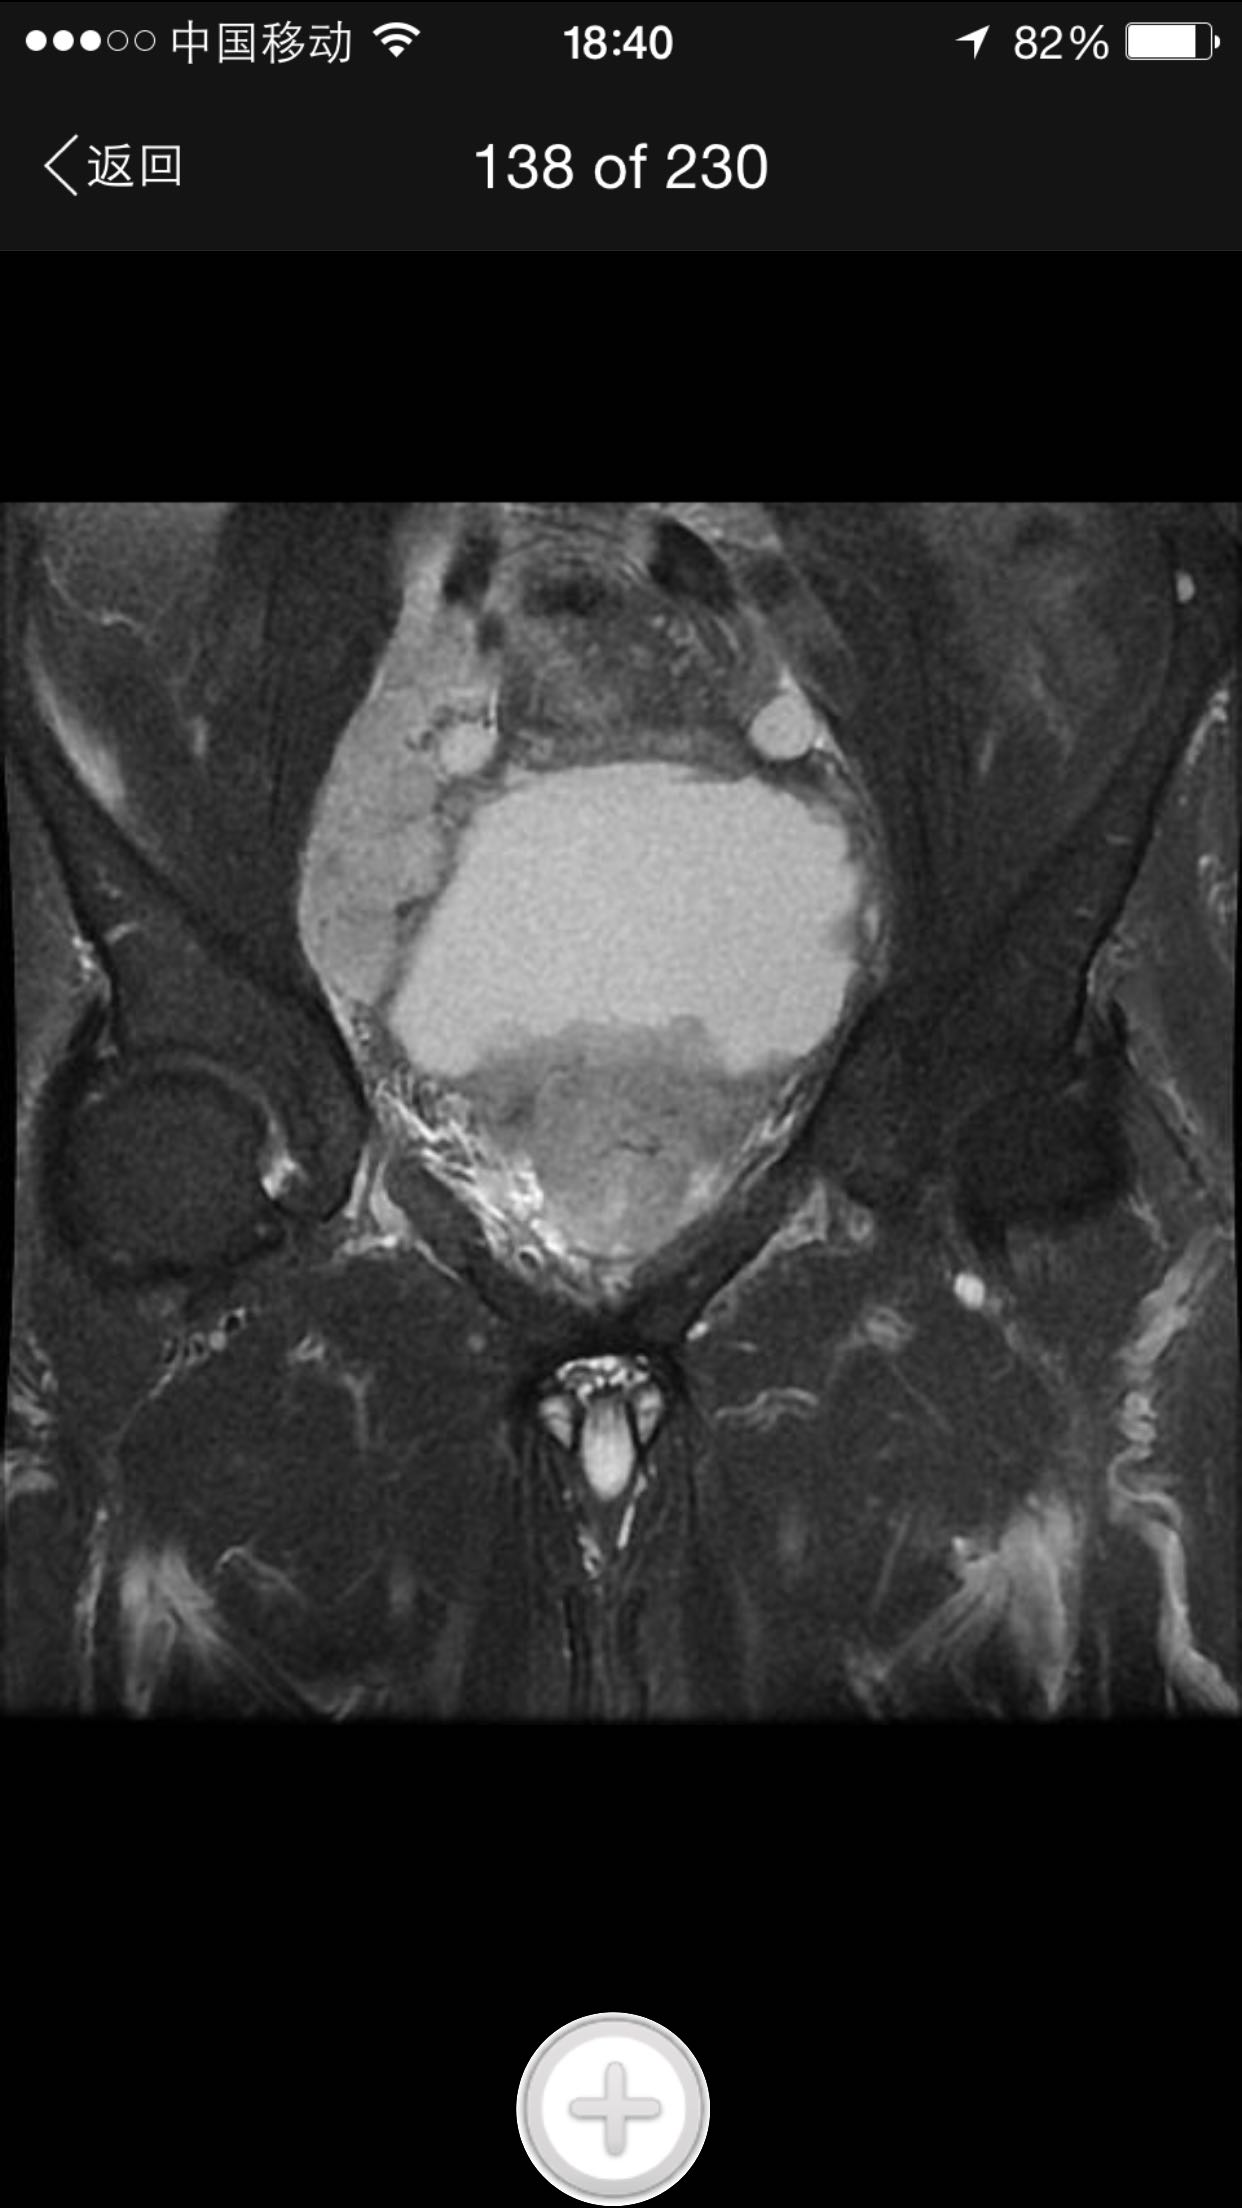

肛诊:前列腺增大,质硬,可扪及多个硬结。 PSA329ng/ml。

诊断:前列腺癌晚期 尿潴留 治疗:考虑患者临床分期较晚,T4期,且淋巴结转移,合并尿潴留,超声提示肾积水,决定行TURP,解决排尿困难。术中快速,如为前列腺癌,直接行手术去势。术中按上述方案处理。术后病理为前列腺中分化腺癌。